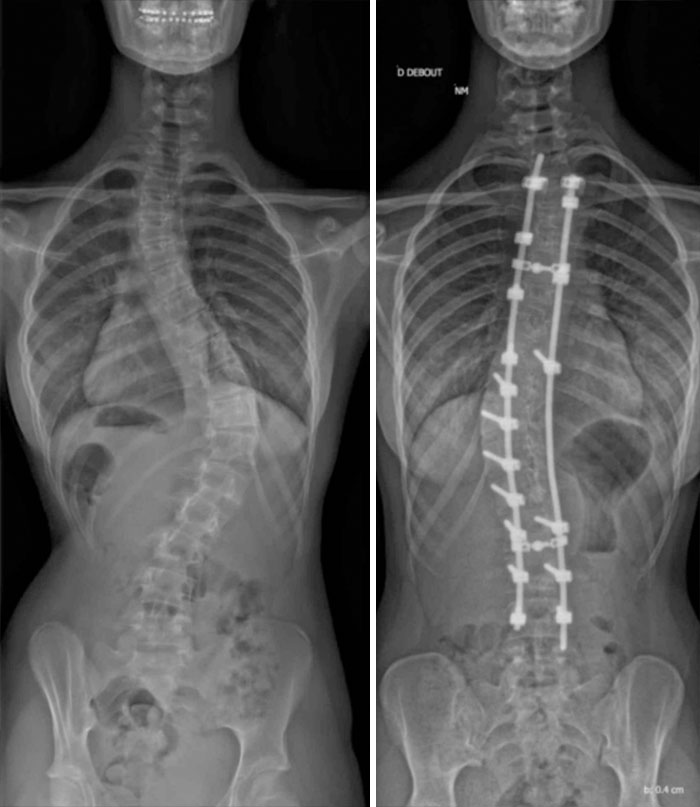

Scoliosis Surgery, Before And After

Can’t imagine how painful and uncomfortable it would be to suffer such significant scoliosis.

X-Rays Before And After Spinal Fusion Surgery For Scoliosis. I Had Surgery At 12 After The Curvature Continued Getting Worse Despite Interventions Being Taken

15 years since surgery and I have no back-related issues. The only issues are caused by the scar tissue from the auto-bone graft from my hip

6 Years Ago Today I Had A Surgery To Straighten Up My Spine, This Is The Before And After Result. I Gained 5 Cm With The Process

X-Rays Of My Spinal Fusion Surgery Before And After